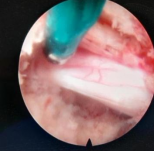

4.微创脊柱内镜技术:PELD+UBE+OSE

脊柱内镜技术是一项开展较早的脊柱外科微创技术,与传统开放手术相比,它是借助天然解剖间隙建立微创工作通道,解除神经压迫;对椎旁肌肉损伤较小,且能够最大程度地保留完整的脊柱结构,维持了术后脊柱的稳定,具有创伤小、出血少、恢复快、并发症少、疗效确切等优点。目前已开展椎间孔镜下髓核摘除术,单侧双通道脊柱内镜(UBE)下椎管减压术并处于区域内领先水平。皇冠娱乐城

在江苏省内率先开展了单孔分体式脊柱内镜技术(OSE),处国内领先水平。

单孔孔镜

单侧双通道技术

单孔分体式内镜下腰椎固定融合技术